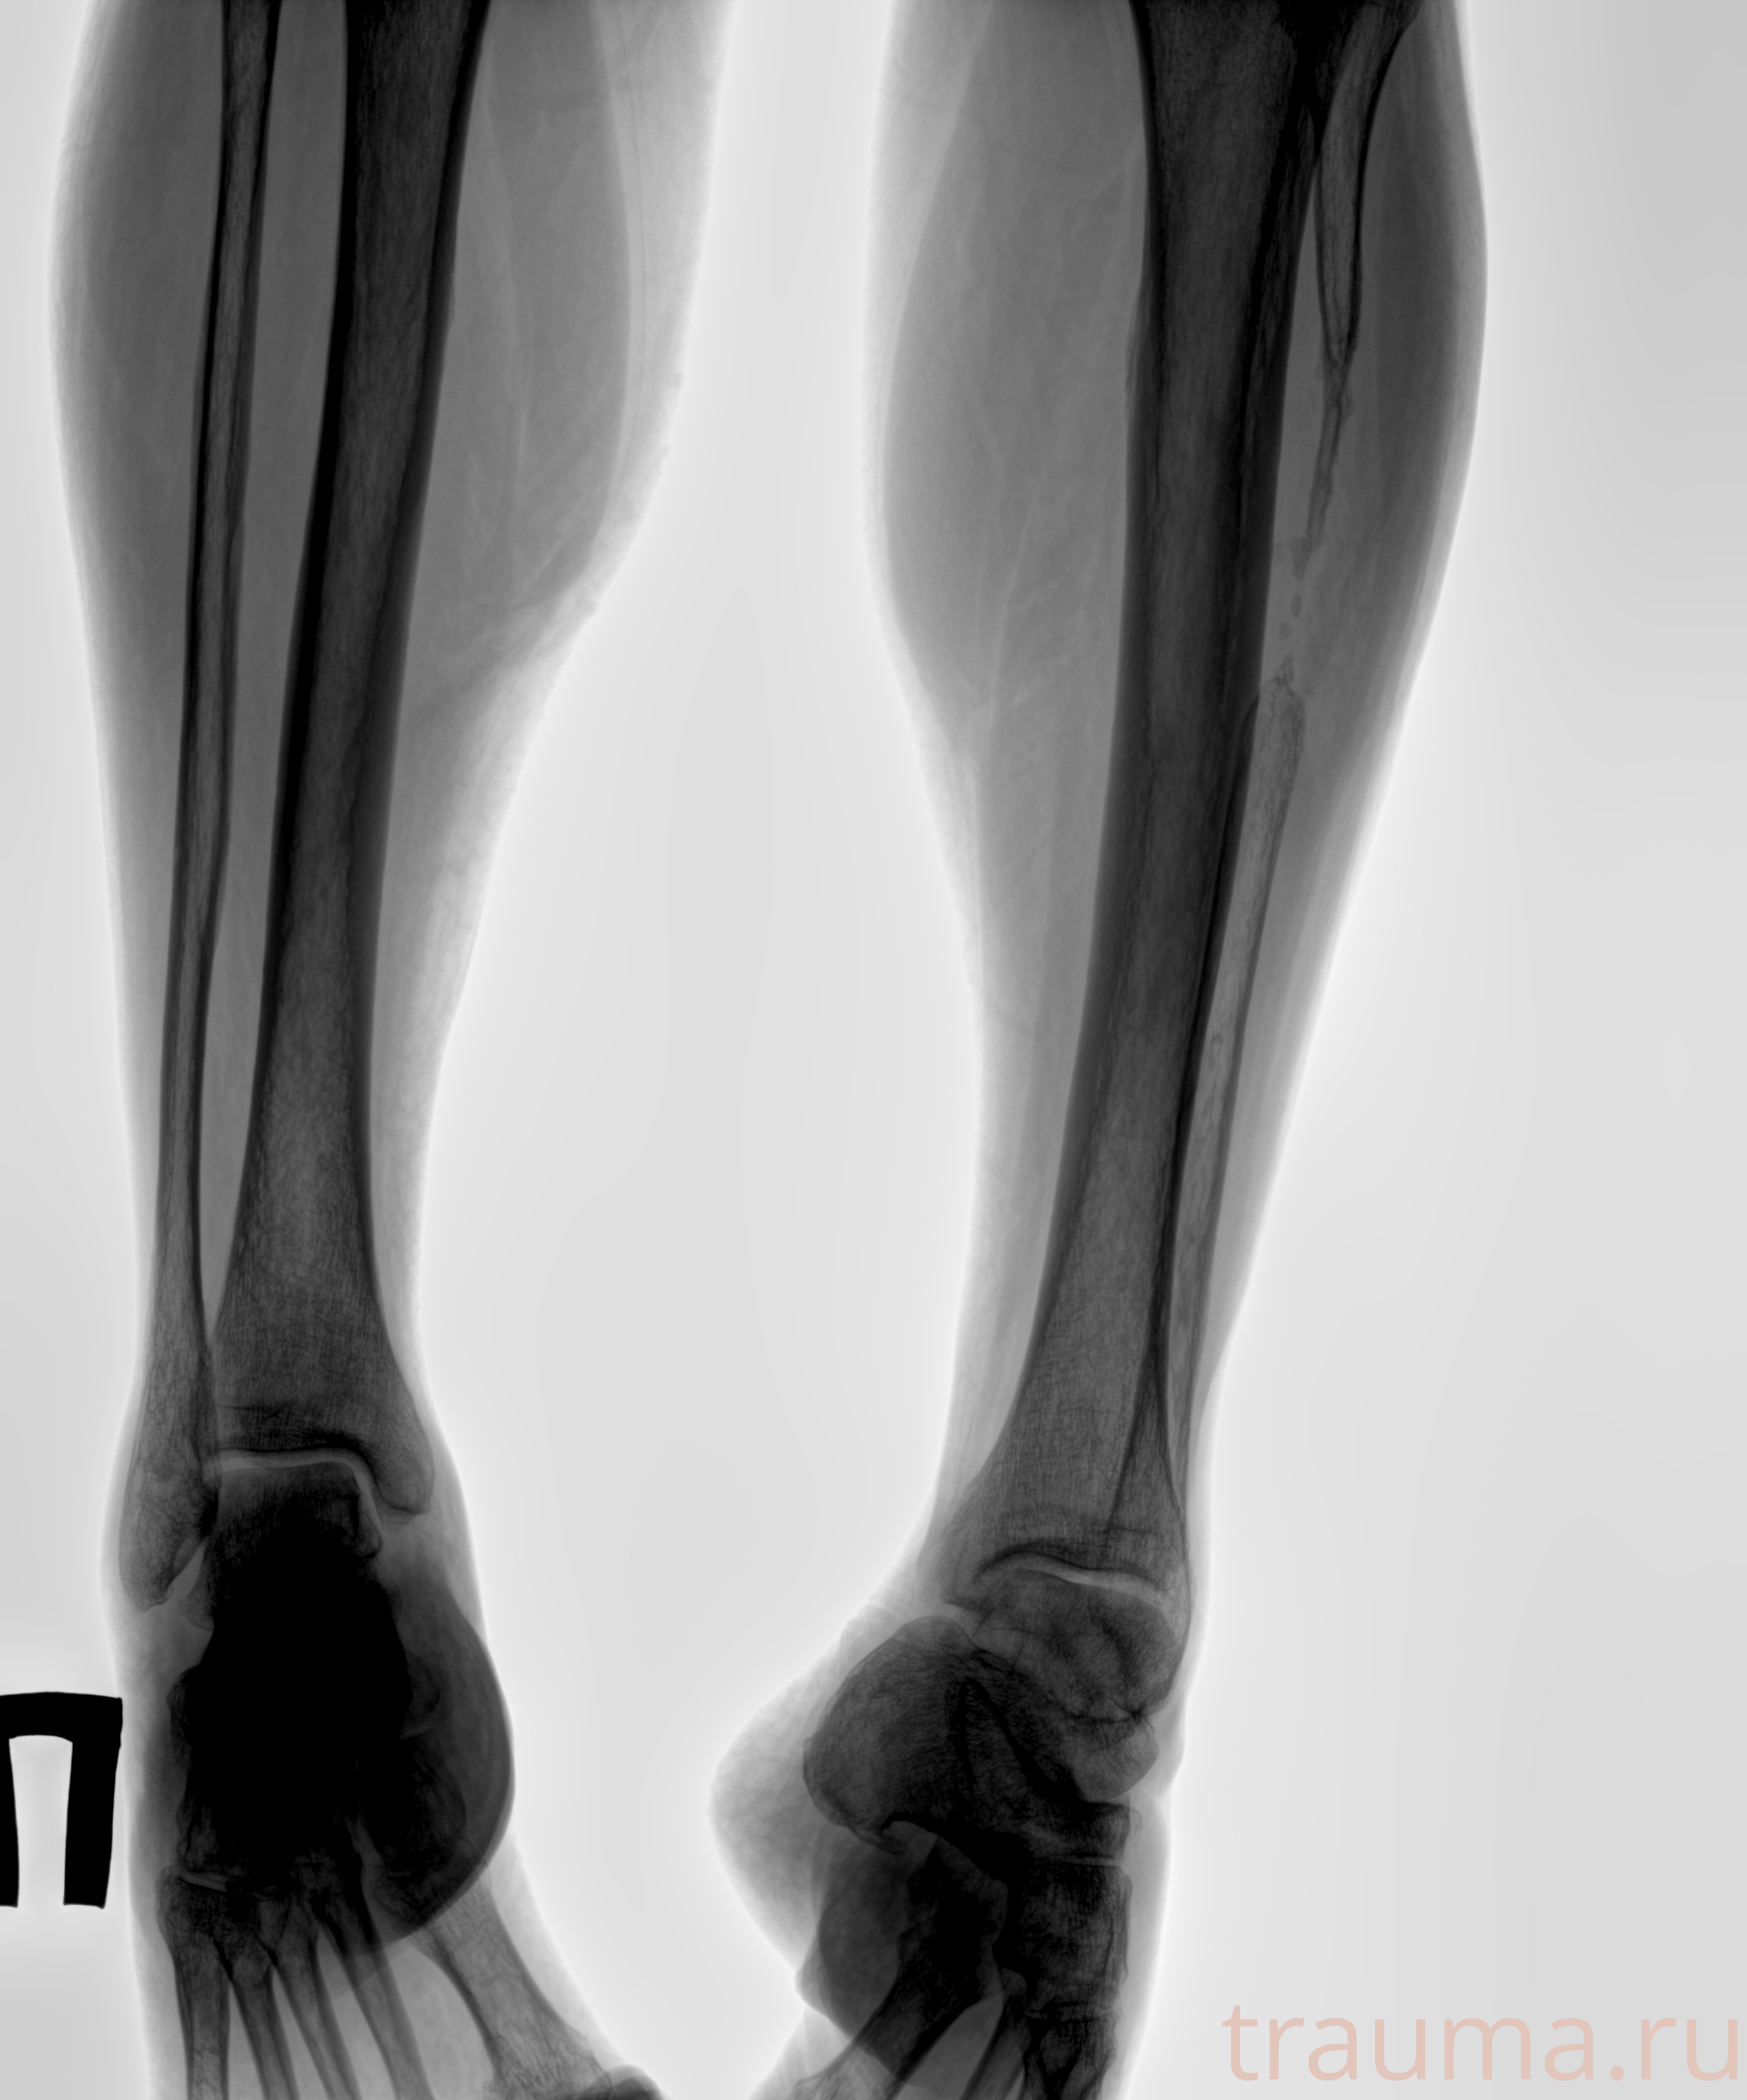

Рентгенограммы

Рентген на дому: по вашему адресу приезжает врач-рентгенолог, травматолог-ортопед с мобильным рентгеновским аппаратом, проводит диагностику травмы или заболевания, делает необходимые рентгенограммы, дает рекомендации по дальнейшему лечению. Получить качественные снимки в домашних условиях возможно благодаря уникальной методике, разработанной МосРентген Центром для института  Склифосовского

Яркость: 1   Контраст: 1   Инвертировать: 0 Увеличение: 1

Перетаскивайте мышь вверх/вниз для контраста, влево/право для яркости. Прокрутка колесом изменяет масштаб. Нажмите Сбросить для возврата к исходному изображению. При увеличении держите мышь в той области, которую хотите рассмотреть.